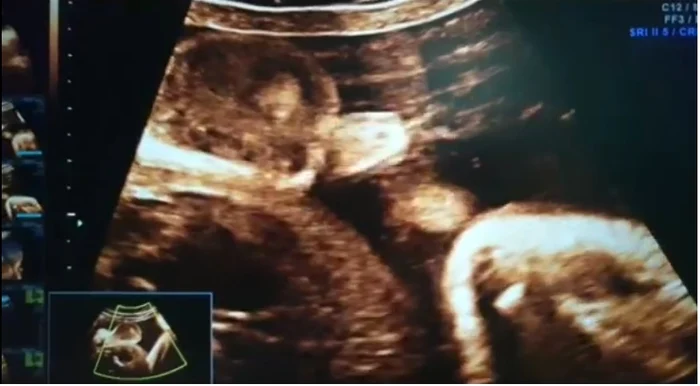

VIDEO Nu te-ai fi aşteptat! Imagini incredibile cu un bebeluş care face pipi în burtica mamei lui

Are doar 30 de săptămâni, iar dezvoltarea lui este normală. Părinţii au venit la un control de rutină. Ecografia urma să le arate şi sexul copilului. Bebe a ales o metodă inedită de a le spune că este băieţel. Medicul ginecolog l-a surprins făcând pipi în burtica mamei lui. Imagini incredibile cu activitatea intrauterină a băieţelului au fost postate pe pagina de Facebook a medicului.

Unii copilaşi sunt mai liniştiţi atunci când medicul îi analizează la ecograf. Alţii sunt mai agitaţi şi nu stau o clipă locului. Băieţelul din imagine are 30 de săptămâni. Se pare că s-a emoţionat foarte tare la întâlnirea cu părinţii şi a făcut pipi. Înregistrarea a fost postată pe pagina de facebook a medicului ginocolog Gheorghe Gică.